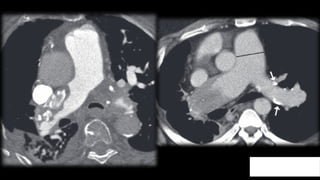

Trombo Crónico

Defecto de

repleción completo

Disminución de

calibre y atrofia

vascular

repleción parcial

Localizarse en la

periferia del vaso

A veces son

concéntricos

Morfología de

banda lineal, red o

trombo mural

excéntrico

Calcificación del

trombo

Aumento de calibre

de las arterias

bronquiales y

colaterales

Menos frecuente

dilatación

segmentaria

bronquial

Imposibilidad de distribuir toda la

volemia de la circulación derecha al

pulmón, aumento de presión y aumento

de calibre de la arteria pulmonar.

Debe ser inferior al de la aorta

ascendente y debe medir menos de 3 cm

5. Hipertensión

Pulmonar

Trombo Crónico Defecto de replecióncompleto Disminución de calibre y atrofia vascular Defecto de repleción parcial Localizarse en la periferia del vaso A veces son concéntricos Morfología de banda lineal, red o trombo mural excéntrico Calcificación del trombo Aumento de calibre de las arterias bronquiales y colaterales Menos frecuente dilatación segmentaria bronquial

Imposibilidad de distribuirtoda la volemia de la circulación derecha al pulmón, aumento de presión y aumento de calibre de la arteria pulmonar. Debe ser inferior al de la aorta ascendente y debe medir menos de 3 cm 5. Hipertensión Pulmonar